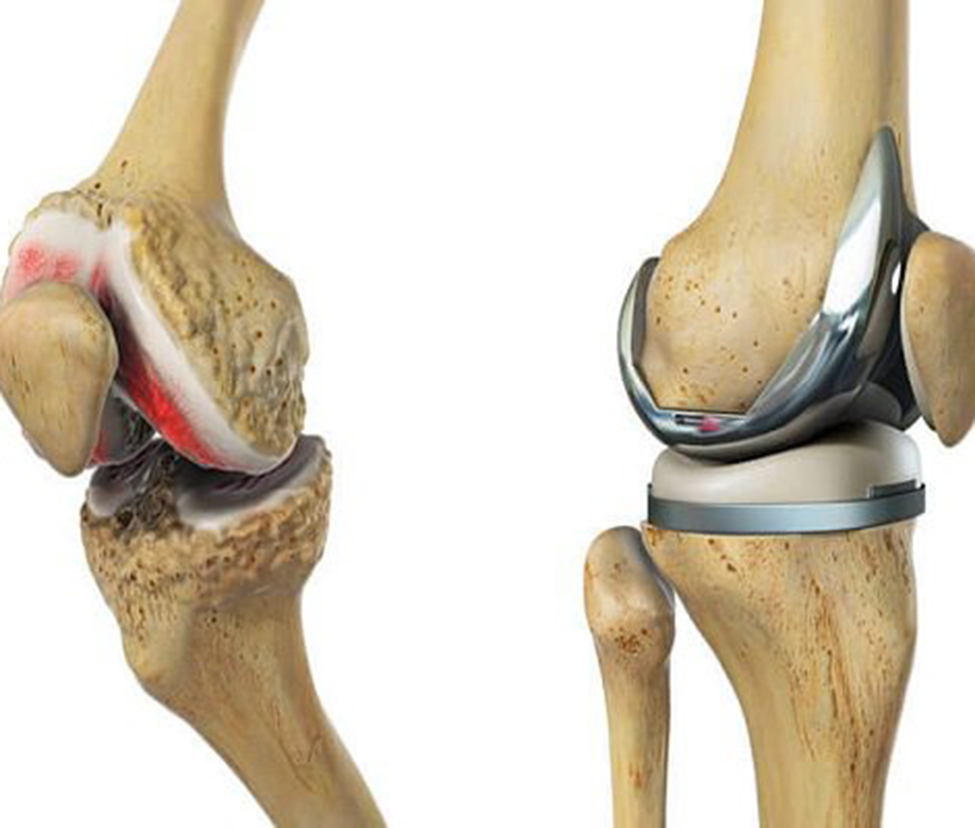

Phục hồi chức năng chấn thương chỉnh hình